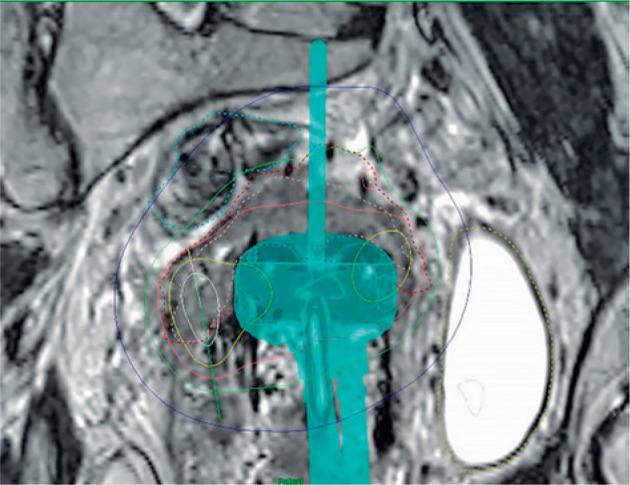

Purpose: Modern applicators in cervical cancer brachytherapy (BT) have an integrated option for using interstitial needles. Even though this allows improved dose coverage in large tumors, there are cases where pre-positioned needle arrangements within applicator are not optimal. In such cases, free-hand needles (FHNs) can be inserted into tumor without using applicator's positions. However, this requires a skilled professional, because the depth of tissue must be estimated without any help of needle insertion tools, and the angle of needle is critical. Improved dose coverage of the tumor and the effect on critical organ doses are yet to be estimated, if they constitute the time used and possible additional complication risk using FHNs.

Material and methods: In this work, clinical brachytherapy treatment plans using FHNs were compared with hypothetical plans, in which the best possible effort was applied to produce acceptable treatment plans without FHNs. Twenty-four cervix cancer patients with FHNs were re-planned without FHNs. Biological total doses were calculated for target volumes (high-risk clinical target volume [HR-CTV], gross tumor volume [GTV], and intermediate-risk clinical target volume [IR-CTV]) and organs at risk. External beam radiation therapy (EBRT) dose distributions were summed to brachytherapy plans, and total doses were compared.

Abstract Image